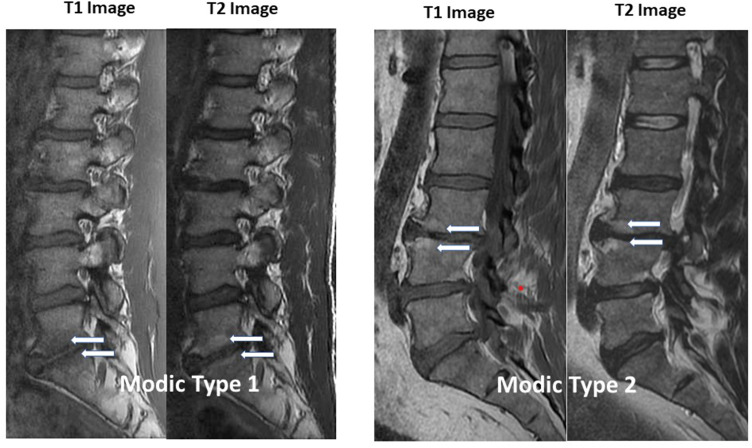

Schematic representation of Modic endplate changes: Type 1 (edema/inflammation, T1 dark/T2 bright), Type 2 (fatty replacement, T1 bright/T2 bright), Type 3 (sclerosis, T1 dark/T2 dark). Types 1 and 2 are associated with vertebrogenic pain.

Modic changes on MRI are the key imaging finding that identifies BVN ablation candidates:

| Type | T1 Signal | T2 Signal | Pathology | Clinical Significance | |------|-----------|-----------|-----------|----------------------| | Modic 1 | Hypointense | Hyperintense | Active inflammation/edema | Best predictor of treatment response | | Modic 2 | Hyperintense | Hyperintense/iso | Fatty infiltration | More chronic/stable; may still respond | | Modic 3 | Hypointense | Hypointense | Sclerosis | Least common; not an indication |

• Modic 1 changes represent active inflammatory endplate disease and are the strongest predictor of response to BVN ablation